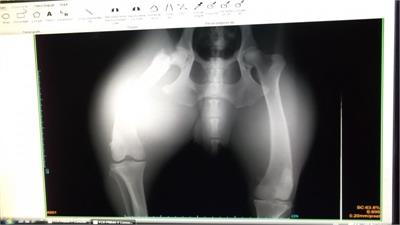

Kangal kırması koca vucutlu  hayvan araba çarpmış mevlanakapı surlarının dibinde yığılmış kalmış bir vatandaş görüyor olayı arıyor xx belediyeyi ama kimse almaya gitmiyor hayvanı ertesi gün işe giderken görüyor ki hayvan aynı yerde yatıyor.Gece ayazında o hayvanın halini düşünmek bile üzüntü verici akşam saati 19.00 gibi barınağa gelip haber verdi hemen araba ayarlayıp hayvanı almaya gittik durumu çok kötü idi acil kliniğe yetiştirdik.Genel durumu kötü olduğu için yogun bakıma alındı 3 gün sonra toparldı hayvan röntgen çekildi ve kalçada kırık olduğu tespit edildi ve ameliyata alındı.İsmini SUR  koydum.Sur kızın ameliyat masraflarına destek bekliyoruz.